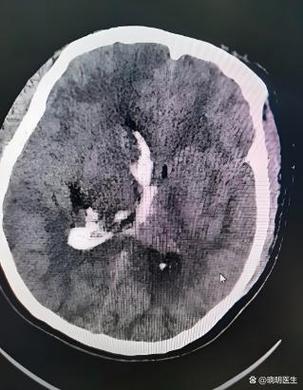

(图片来源网络,侵删)